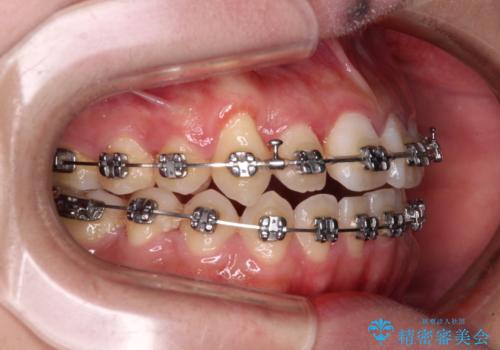

- メタルブラケット

上顎歯列が狭窄していたため、急速拡大装置により上顎骨を側方に拡大し、その後ワイヤー装置にて矯正治療を行うこととしました。

上顎骨を拡大することで、八重歯やデコボコを歯列に収めることができ、下顎の歯が外に位置していた奥歯の咬み合わせも改善することができました。

スペースも短期間に獲得できるため、1年程度で治療を終えることができました。